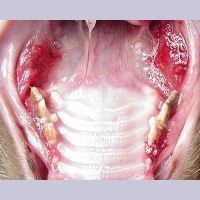

Image 7.10. 중증 gingovo 구내염

Image 7.11.Lymphocytic-Plasmacytic Gingivitis Stomatitis (LPGS)